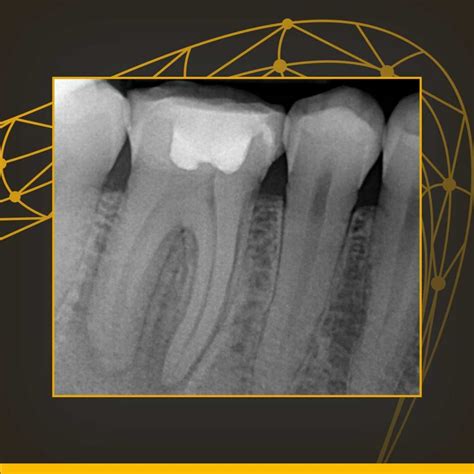

A Periapical X Ray, often referred to simply as a "PA," is a close-up, high-resolution diagnostic image. The term "periapical" literally translates to "around the apex," with the apex being the tip of the tooth root. This specific type of X-ray is designed to show the entirety of the tooth—from the biting surface (crown) down to the root end—as well as the surrounding supporting bone.

Because it offers such fine detail, dentists utilize this scan to diagnose specific problems that might be missed by broader imaging methods. Whether you are experiencing localized pain, sensitivity, or require a procedure that demands precision, this X-ray is often the first step toward an accurate diagnosis.

One of the most frequent questions patients ask is about the safety of radiation. It is important to understand that the radiation dose from a modern Periapical X Ray is extremely low. Dentists follow the ALARA principle—"As Low As Reasonably Achievable"—to ensure that patients receive the minimum amount of radiation necessary for a high-quality diagnostic image.

Digital radiography has significantly reduced the radiation dose compared to older, film-based X-rays. Furthermore, the focus of the beam is highly targeted, meaning radiation is not scattered across your entire head. The benefit of diagnosing a serious infection or decay far outweighs the minimal risk associated with the diagnostic scan.

Choosing to move forward with a recommended Periapical X Ray can be a crucial decision for your long-term oral health. By catching issues early—such as a small fracture or an incipient abscess—you can often avoid more invasive and expensive treatments later on. For example, treating a minor infection at the root tip is significantly simpler than managing a full-blown dental emergency caused by a neglected abscess. This diagnostic tool allows your dentist to practice proactive, rather than reactive, dentistry.